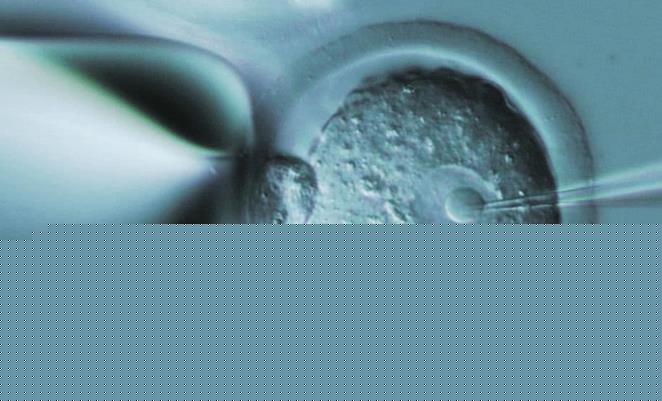

是否存在遺傳缺陷的基因,是一種結(jié)合 ART和分子生物學(xué)技術(shù)的產(chǎn)前診斷技術(shù)。在體外,精子卵子形成受精卵,發(fā)育成胚胎。在胚胎移植到母體子宮時(shí)接受基因檢測,確保試管嬰兒不會(huì)患上遺傳性疾病。

深圳市婦幼保健院是可以做三代試管的,并且是在2019年獲批可以開展胚胎植入前遺傳學(xué)檢測(PGT)的。除了可以開展三代試管嬰兒技術(shù)之外,該院目前開展的輔助生殖助孕項(xiàng)目有夫精人工授精、常規(guī)體外受精-胚胎移植(第一代試管嬰兒)、卵胞漿內(nèi)單精子注射(第二代試管嬰兒)。